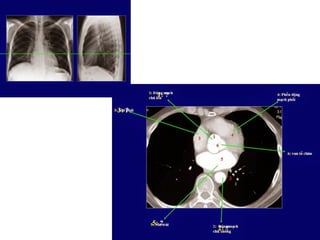

Case 1: Bệnh nhân nam 70 tuổi, vào viện với bệnh cảnh đau ngực nhiều ngày,

siêu âm dãn thất phải, tăng áp đm phổi. CT huyết khối động mạch phổi nhánh

chính 2 bên (mũi tên).

- Bệnh nhân được chuyển BVCR. Chẩn đoán tắc động mạch phổi 2 bên.

57

- Động mạch phổi gốc, nhánh phải và trái không dãn…khả năng là tắc mạn tính.

Đm phổi gốc Đm chủ